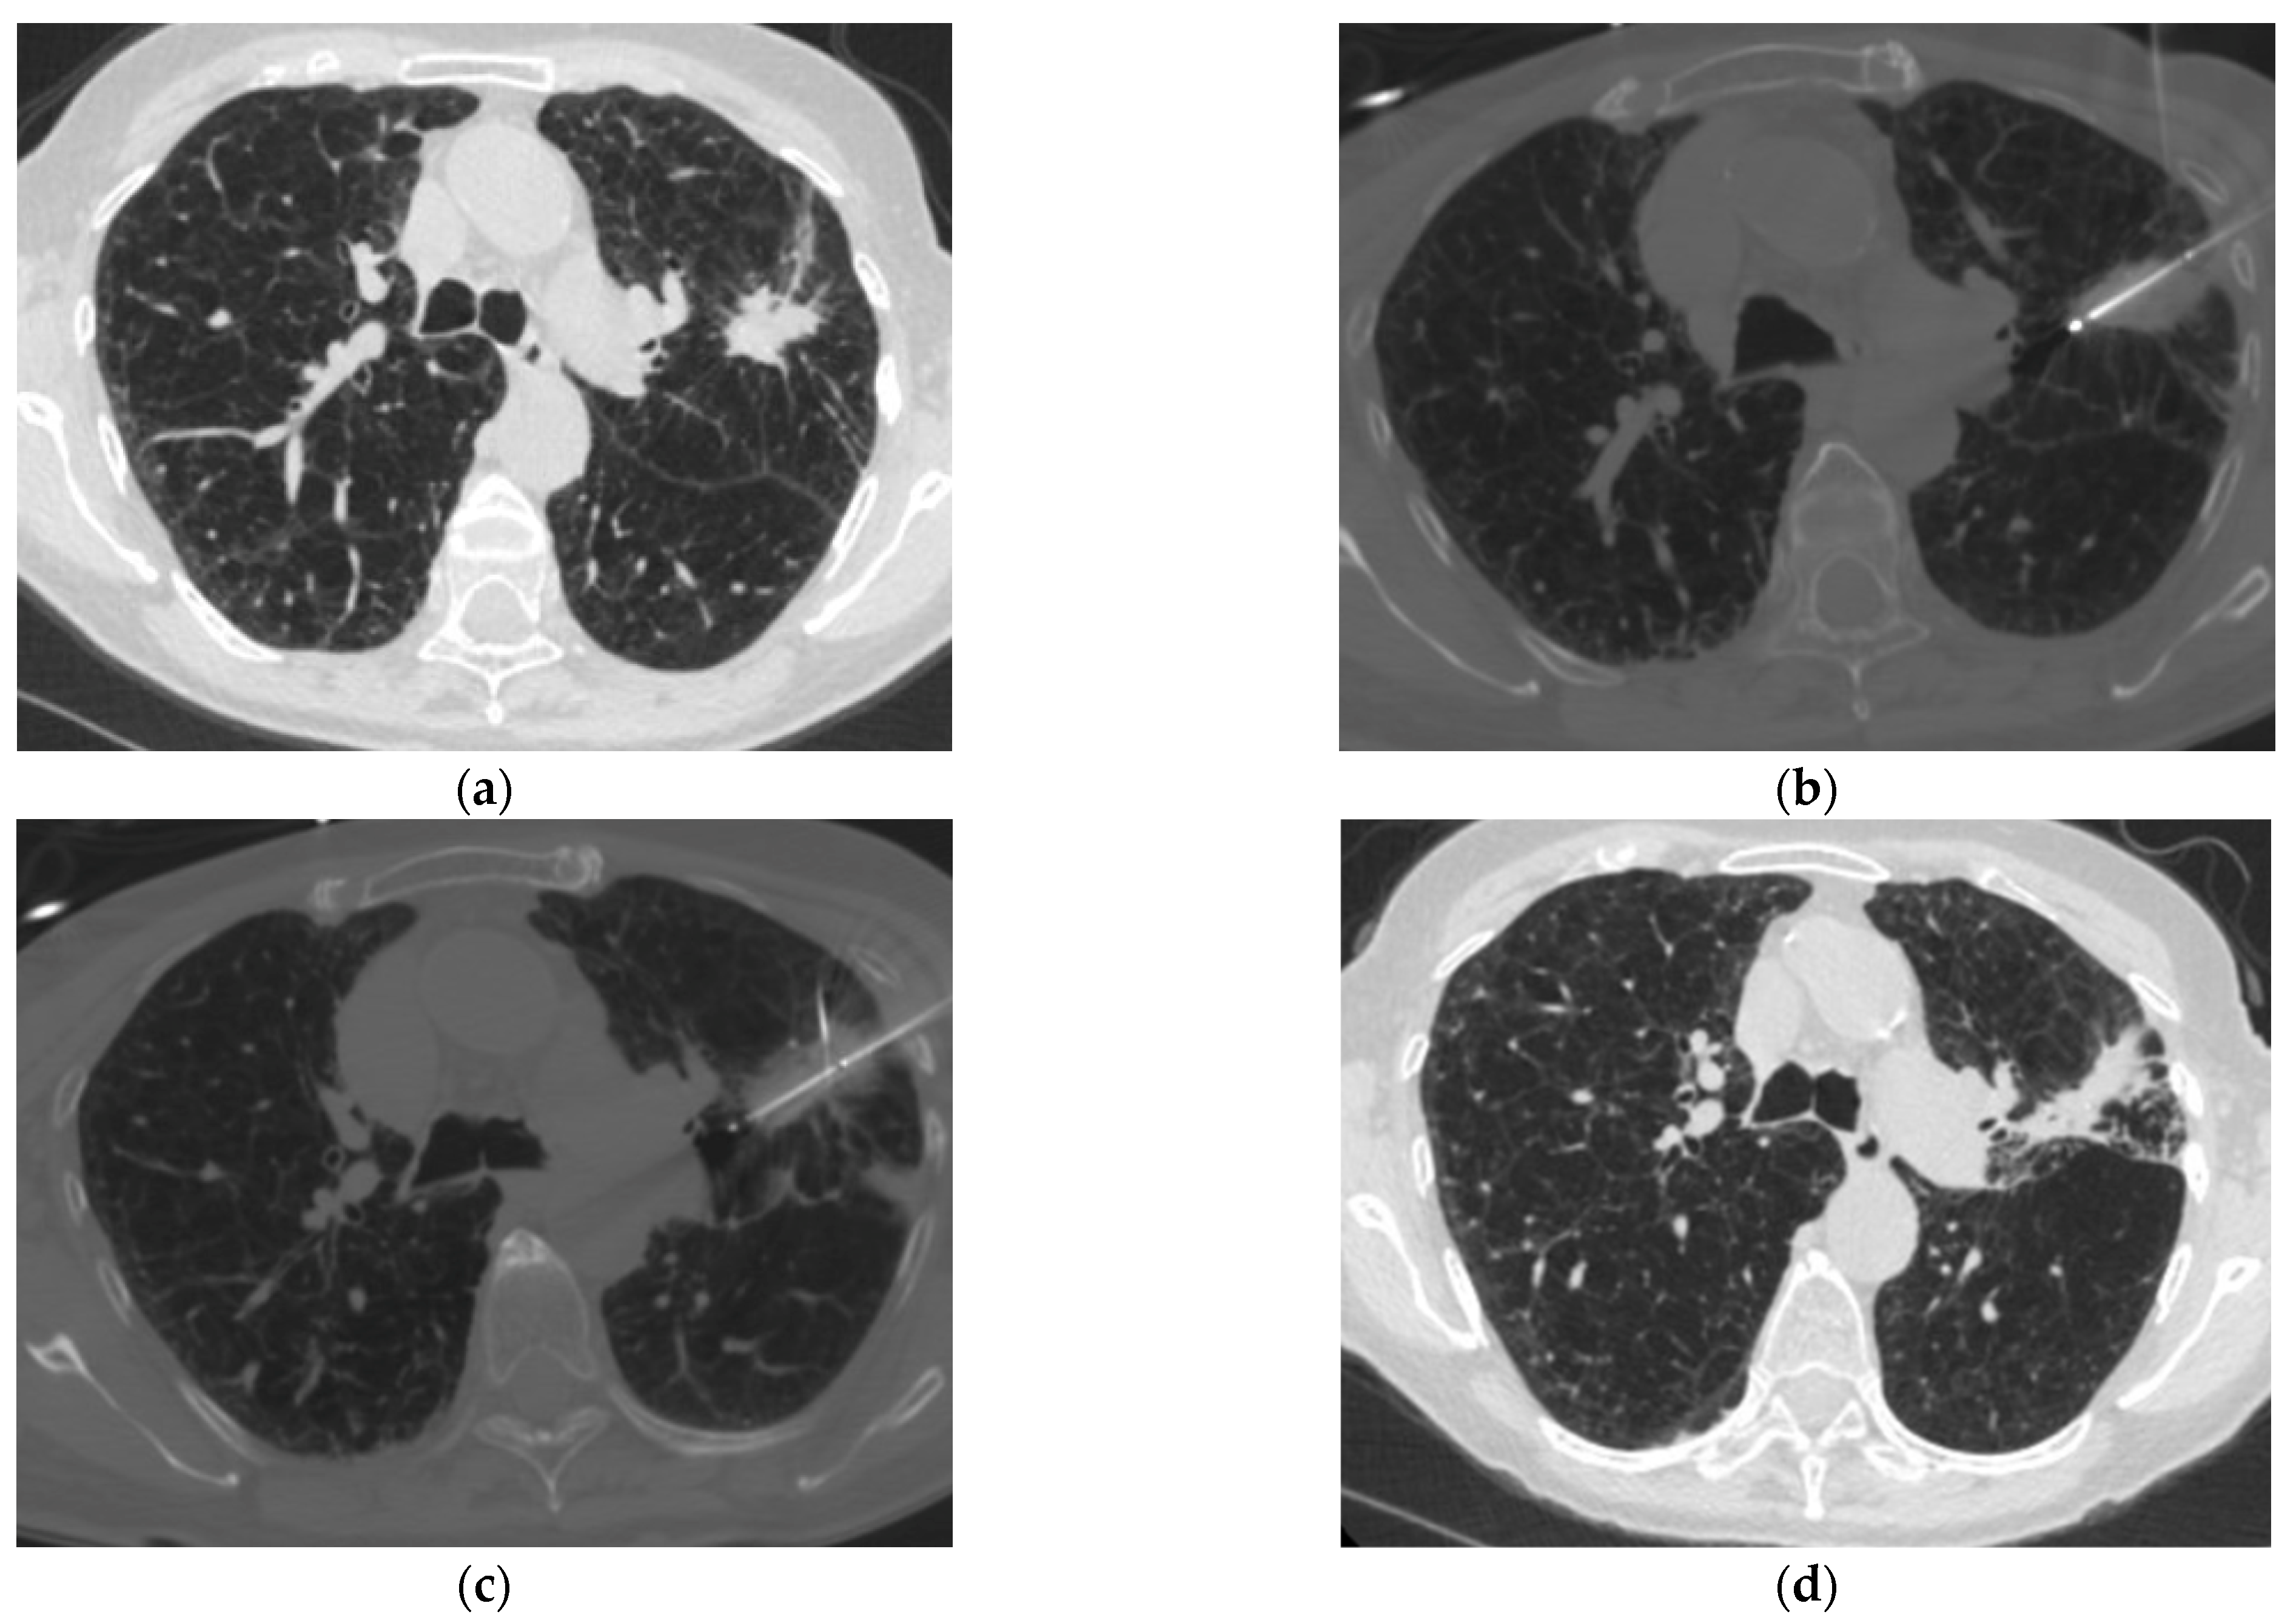

3. Advances in Image Guidance and Navigation

3.1. Cone Beam CT with Image Fusion

3.2. Electromagnetic Navigation-Assisted Ablation

3.3. Robotic-Assisted Ablation

- Chang, L.-K.; Su, P.-K.; Malwade, S.; Chung, W.-Y.; Chan, P.-S.; Chen, S.-C.; Chen, L.-C.; Yang, S.-M. Enhancing Microwave Ablation for Lung Lesions with Cone-Beam Computed Tomography Guidance and Intrapulmonary Fine Adjustment in a Hybrid Operating Room. Acad. Radiol. 2025, 32, 7591–7600. [Google Scholar] [CrossRef]

- Li, S.; Bie, Z.; Li, Y.; Sun, J.; Zhang, J.; Zi, X.; Guo, R.; Li, X.-G. Electromagnetic Navigation System for Computed Tomography-Guided Synchronous Percutaneous Lung Biopsy and Microwave Ablation of Pulmonary Nodules: A Prospective, Single-Center, Single-Arm Clinical Study. Int. J. Hyperth. 2024, 41, 2417761. [Google Scholar] [CrossRef]